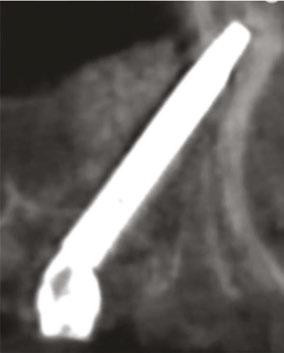

Figure 7 (left): CBCT slice (sagittal view) for vertical measurement from subnasal bone to prelacrimal bone engagement point. Figure 8 (middle): Panoramic radiograph of patient with history of failed All-on-X treatment, oroantral fistulae, and thickened Schneiderian membranes. Figure 9 (right): Intrasurgical photo of transnasal dental implant traversing the nasal cavity and engaging the base of the inferior concha

Following PATZi, anterior support was sought next. As such, the nasal mucosa was elevated to expose the floor of the nasal cavity and the bone of the inferior conchae. A pair of 25 mm transnasal implants were placed, and each achieved high insertion torque of 45+ Ncm (Figures 9-11). Continuing with the PATZi protocol and treatment plan, 42.5 mm long zygomatic implants were placed in both zygomas. The zygomatic implants were placed using an extrasinus approach and both achieved insertion torque of 45+Ncm. Buccal fat pedicles were advanced bilaterally to cover extrasinus portions of the zygomatic implants, and flap closure was achieved with 4-0 chromic gut suture. The patient was immediately temporized with a screw-retained transitional bridge (Figure 12), and a final zirconia restoration was delivered after 8 months of healing (Figure 13).

Figure 10 (left): CBCT slice (coronal view) of transnasal dental implants engaging the Z-point. Figure 11 (middle): CBCT slice (sagittal view) of transnasal dental implant engaging prelacrimal bone ventral to the nasolacrimal duct. Figure 12 (right): 3-dimensional CBCT rendering of patient treated with transnasal, zygomatic, and pterygoid dental implants via the PATZi protocol